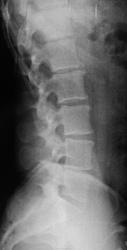

Задняя нестабильность L2,4 первой степени. Охватывающие остеофиты - за передние "хрящевые узлы" дисков. Повышенная прозрачность L2 в боковой требует по минималке томограммы, хотя деструктуризации не видно.

Остеохондроз поясничного отдела позвоночника, 2-3 период. Ретролистез L2? Я бы заказала снимки с функциональными пробами. На счет измененной структуры L2,это не пневмат.петли кишечника?

Выпрямление поясничного кифоза,наличие остеофитов по передне-боковым поверхностям L1,L2,склероз суставных поверхностей.При необходимости рекомендовано МЭРТ.

Измененная структура тела L2 позвонка?